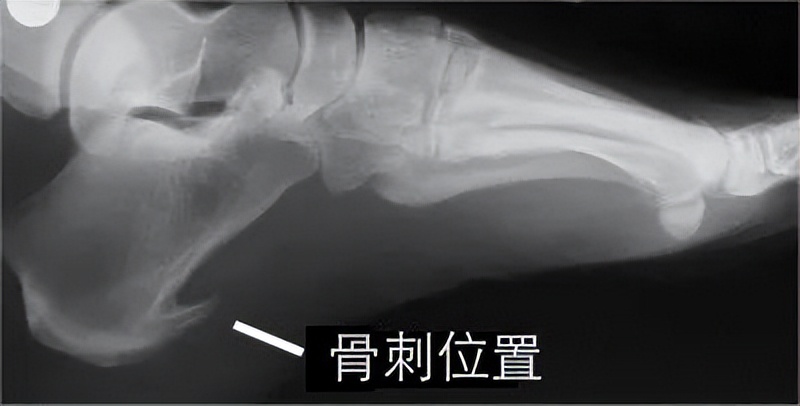

如果跖筋膜附着在跟骨结节处的创伤性炎症反应长期存在,就会刺激跟骨的骨膜,造成骨质增生,形成 鸟嘴样的骨刺 ,骨刺在足负重时,可以对足底软组织产生机械性压迫而疼痛。

骨刺形成之后一般是不会被吸收的,但经过治疗,足跟痛的症状可以消除。